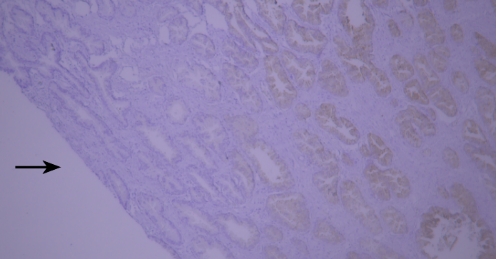

(V) Tissue Drying IssueTypical example:

TIMP-1 staining of paraffin-embedded human prostate tissue sections showed false negatives due to tissue drying (indicated by black arrows).

Recommendation for Resolution: Using a buffer supplemented with Tween-20 can effectively prevent section drying.

(VI) Edge Effect IssueTypical example:

Lysozyme staining of paraffin-embedded human tonsil tissue sections showed non-specific staining due to edge effect (indicated by black arrows).

Recommendation for Resolution: Ensure firm adhesion between tissue sections and glass slides, and completely cover the tissue with reagents to prevent section drying; using a buffer supplemented with Tween-20 can reduce the occurrence of edge effect.